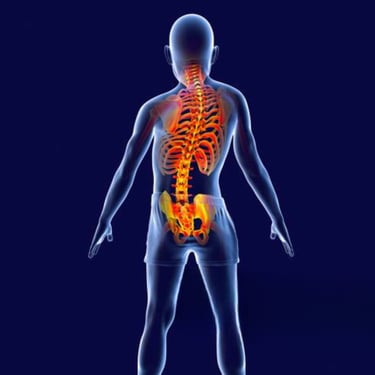

La escoliosis del adolescente idiopática del es una curvatura anormal de la columna vertebral que aparece durante el crecimiento, sin causa identificable. Su diagnóstico se realiza mediante evaluación clínica y estudios por imágenes, principalmente radiografías de columna completa, que permiten medir el ángulo de Cobb y determinar la magnitud de la desviación. En casos complejos o con sospecha de compromiso neurológico, se utiliza resonancia magnética para descartar anomalías medulares. La detección temprana es clave para definir el tratamiento adecuado —observación, uso de corsé o cirugía— y prevenir la progresión de la deformidad.